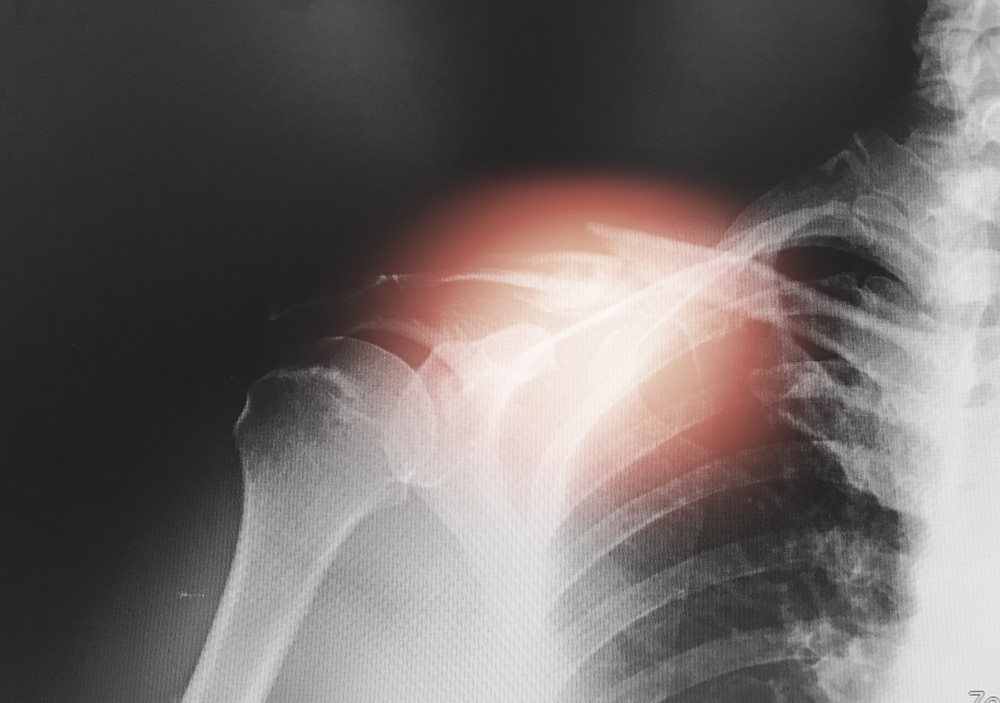

Does Rotator Cuff Pain Radiate Down The Arm?

Yes, rotator cuff pain can sometimes radiate down the arm. The rotator cuff is a group of muscles and tendons that surround the shoulder joint, and when it’s injured or inflamed, it can cause pain that travels along the arm.

The pain may be felt in various areas depending on the specific location and nature of the rotator cuff injury, but it commonly radiates down the side or front of the upper arm. It can also extend into the forearm or even the hand in some cases. This pain often worsens with certain movements of the shoulder or arm, such as reaching overhead or lifting objects.